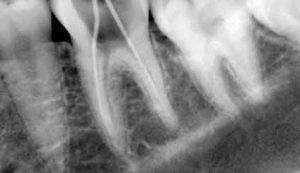

In most cases a clinical exam by itself is not sufficient to completely diagnose all potential problems with your mouth. In fact, the majority of problems with your teeth and the jawbone are not visible to the naked eye. That is why x-rays play a key role in allowing a better, and more accurate look at what is really going on inside your mouth and below your teeth and gums. By using x-rays your dentist can check for any bone loss and determine the severity of the gum disease.

In addition to revealing any problems that were not visible during the clinical exam these initial x-rays will also provide your dentist with a benchmark with which to compare against during your future visits.